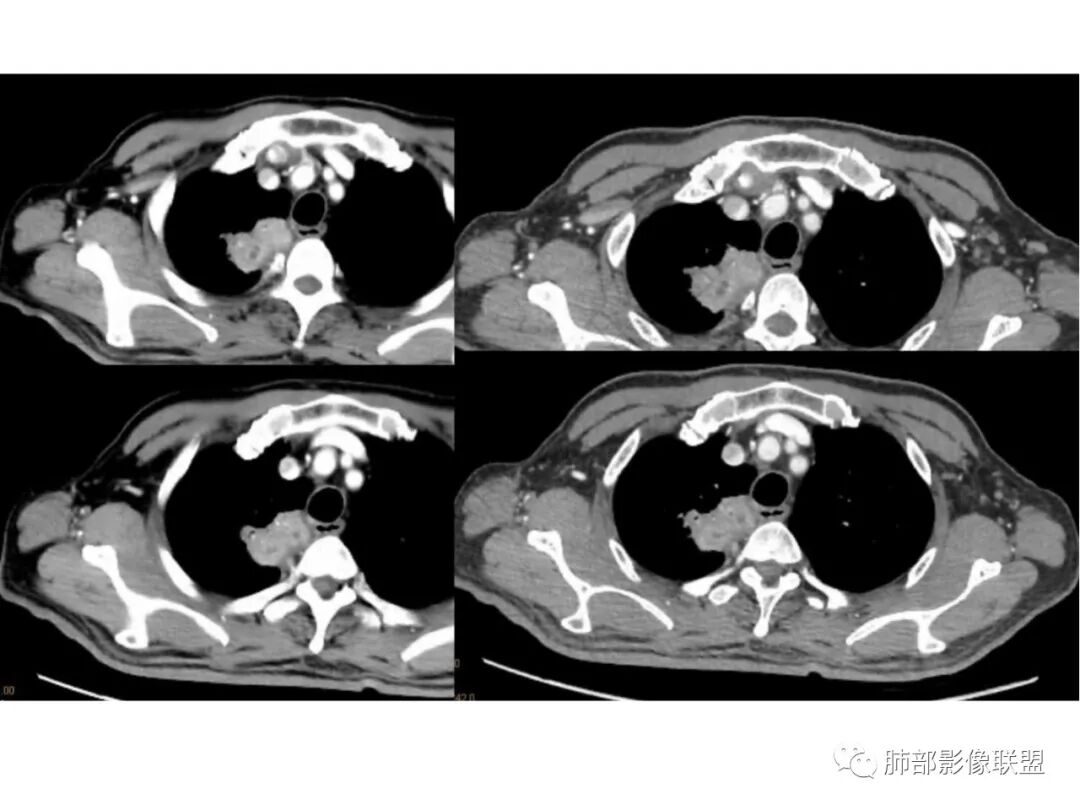

红日初升:老年男性,干咳十天,无发热,血象、肿标不高。右肺上叶团片,叶段分布,边缘多平直凹陷,强化见三层结构,考虑脓肿。边缘局部膨隆,近侧支气管阻塞,恶性不能排除,建议治疗后复查

丽:老年男性,急性病程,右肺上叶团片状高密度影,边缘有膨隆也有平直,胸膜下脂肪间隙消失,增强后明显强化,静脉期持续强化,并见条形低密度影无强化,考虑慢性炎症,建议抗炎治疗后复查除外恶性

爱跳舞的猫:老年男性,干咳,无发热,血象、肿标不高。右肺上叶团片影,呈条状,边缘多平直,增强扫描明显强化,其内见无强化坏死区,内壁光滑,考虑脓肿,建议治疗后复查除外恶性

凝睦:右肺上叶团块,边缘平直,胸膜糊墙,明显强化,内部血管走行自然,支气管粘液栓,考虑炎性。

采莲:老年男性,干咳,有吸烟史,右肺上叶不规则肿块,边缘平直收缩为主,,有细软毛刺,靠近纵隔边缘,明显强化,内有粘液栓,近端支气管阻塞,阻塞端圆盾,无明显胸膜增厚,感觉既有恶性征象,也有良性征象,血象不高,血沉快,肿标不高,但患者有吸烟史,主要是炎症和肿瘤鉴别,首选炎性肉芽肿,鉴别肺癌,毕竟有肺气肿背景,肿瘤不排除。建议穿刺。

王江涛:边缘平直,明显强化,血管穿行,部分支气管扩张积液,胸膜糊墙,支持炎性病变,结核不除外。

宇宙:右肺上叶纵隔旁肿块,形态欠规整,边缘平直为主,周围长索条,邻近胸膜增厚,明显强化,血管未见破坏,其内支气管粘液栓,考虑炎性肉芽肿

陈学君:右肺上叶实变灶,边缘平直为主,胸膜糊墙,强化较明显,似有支气管粘液栓,考虑慢性炎症。

红星:老年男性患者有长期的吸烟的病史,临床症状是干咳。影像学表现右上肺胸膜下的分叶状的结节,密度欠均,内部见小灶性的坏死以及支气管空泡征,增强扫描呈明显的强化,从重建的图像来看,病灶的上下径较长,并沿着支气管的长轴生长,纵隔内无明显的肿大淋巴结。考虑肉芽肿性病变,结核性病变?炎性?鉴别诊断:肺鳞癌。

秦化君:老年男性 刺激干咳,右肺上叶纵隔胸膜下不规则软组织密度团块影。边缘部分膨隆、凹陷,可见分叶、毛刺。矢状位似可见支气管堵塞截断。肿块相邻胸膜栽桩,似侵及气管壁(刺激性干咳的原因)。增强后中等以上强化,内见条状无强化影(粘液栓?)。综合考虑恶性病变可能大。炎性肉芽肿待排。

放射线:右肺尖不规则肿块,有分叶毛刺,有胸膜栽赃,冠状位可见支气管粘液栓,矢状位病灶呈外朝内沿支气管分叉角生长,强化明显,考虑腺癌,鉴别炎性肉芽肿病变。

旁观者:老年男性,长期大量吸烟,刺激性干咳,无发热及胸痛,感染指标及肿瘤标记物阴性,影像,右肺上叶靠近纵隔长条状病灶,边缘收缩,长毛刺,明显强化,见粘液栓,支气管情况不好评估,无磨玻璃及树芽,纵隔淋巴结不大且无钙化,胸水无。建议支气管镜排除气道占位性病变,或者外朝内病变,结核或者腺癌,感染性病变OP伴脓肿,老年,吸烟,首先排除癌

飞鹰行动:老年男性,咳嗽入院,影像表现右肺上叶实变病变,局部边缘平直凹陷,与胸膜相贴,未见胸膜牵拉,近端支气管壁增厚,支气管进入病灶后阻塞,增强病灶强化较明显,内见支气管粘液栓,考虑慢性炎性病变,结核不排除。

周太狼:老年男性,吸烟,急性病程,右肺上叶团片状高密度影,边缘收缩膨隆,长毛刺,增强后明显强化,内见少许条形低密度影无强化区,支气管似有阻塞,考虑慢性炎症,建议抗炎治疗后复查除外肿瘤病变

衡妈:老年男性,右肺上叶尖段沿支气管走形片状实性密度,平扫密度相对均匀,横断面显示有明显平直、凹陷边,与周围肺野界限清晰,少许长软毛刺,与侧胸膜宽基底相连,未见明显支气管堵塞;增强后明显延时强化,强化不均匀,可见小灶性坏死,所见纵隔未见肿大淋巴结。考虑慢性炎性病变,炎性肌纤维母细胞瘤?鉴别腺癌。

小兜:老年男性,既往吸烟史,刺激性干咳十余天入院,血象及肿标未见异常。CT示右肺上叶脊柱旁不规则实变影,平扫密度较均匀,增强扫描呈渐进性明显强化,内部可见粘液栓。支气管进入病灶后狭窄阻塞,综合考虑为炎性病变

了:右肺上叶肿块影,边缘清楚,纤维条索影,均匀强化,内可见低密度坏死影,考虑慢性炎性肉芽肿

看图说话:右肺上叶团块状影,气管堵塞,边缘膨隆,密度不均,内见坏死,粘液栓,胸膜栽赃,增强后明显强化,考虑慢性炎症,鉴别腺癌。

安吉木子何方李:良恶性征象都要,感觉支气管鼠尾样狭窄,明显强化,还是先考虑恶性肿瘤。患者有支气管粘液栓,无强化,炎性肉芽肿需要考虑

?????天涯?????:内有小片状低密度影,强化这么显著,大概又是个肉芽肿性炎或脓肿之类的,建议抗炎治疗后复查,除外恶性肿瘤性病变鳞或腺癌可能。

信人生:老年男性,急性病程,右肺上叶尖后段团片状高密度影,明显桃尖征象,胸膜下脂肪间隙消失,增强后明显强化强化值约60HU,静脉期持续强化,并见条形低密度粘液栓,化验肿标及结核抗体均阴性,白细胞不高,考虑炎性肉芽肿/慢性炎症,建议抗炎治疗

右上叶尖段带状实变影

外围大、内带小,宽基底与胸膜相连,附近卫星灶

支气管进入病灶内,广泛胸膜增厚

支气管粘液栓

血管走形自然

实变区强化较均匀,明显强化

边缘平直为主

支气管堵了,但是远端粘液栓:是粘液栓堵塞?还是狭窄或堵塞后继发粘液栓?

病灶是支气管腔内堵塞导致远端实变、不张?还是外围病灶融合、实变影响近端支气管?

整体考虑肿块应该不支持,因为支气管、血管走形还算自然,只是收缩在一起,如果肿块走形不会这么自然,会推移、变形,侵犯

现有的图显示近端支气管还是连续的,只是远端扩张,腔内粘液栓,其实还应当看重建的支气管连续的图,与近端含气部分的连续